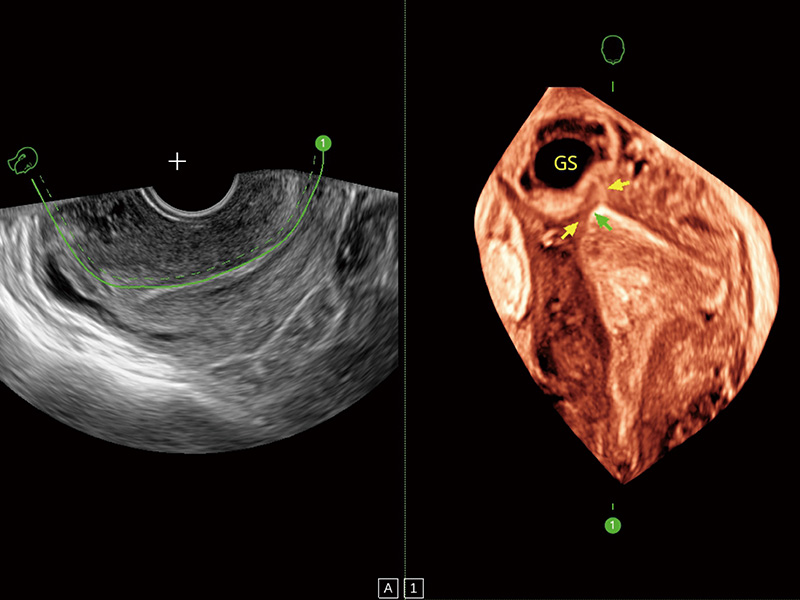

临床图

超声引导下双侧卵巢穿刺取卵

中央型宫腔粘连

子宫内膜息肉